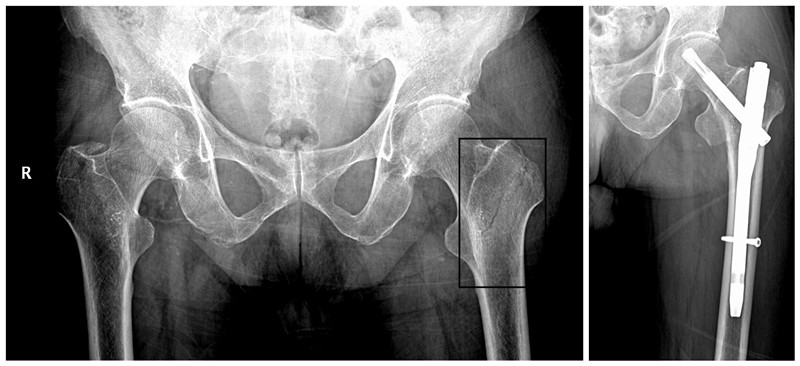

通过术前评估、血糖控制,在入院后的第三天赵顺吕医疗团队为患者进行了左肱骨切开复位内固定、左股骨转子间骨折闭合复位PFNA髓内钉手术。手术顺利结束,谢阿公返回病房,左臂的钢板与左腿的PFNA钉沉默地宣告着医学的胜利,但真正的考验才刚刚开始。病房里,时间被切割成无数个“第一次”:第一次抬腿时谢阿公额角的冷汗、第一次握紧助行器泛白的指节、第一次在护士搀扶下尝试重心转移时颤抖的呼吸……当谢阿公颤巍巍迈出第一步时,他的嘴角漏出了久违的微笑。

术前术后影像学